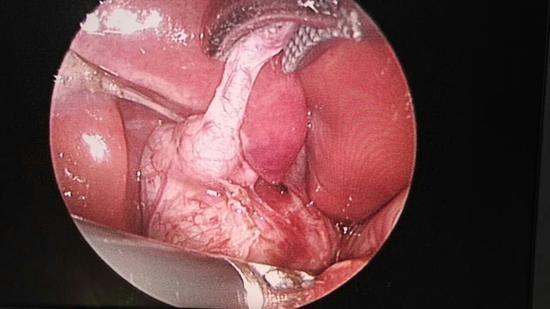

【新浪医讯】哈市儿童医院普外一科为出生42

【新浪医讯】哈市儿童医院普外一科为出生42

【新浪医讯】哈市儿童医院普外一科成功为4岁